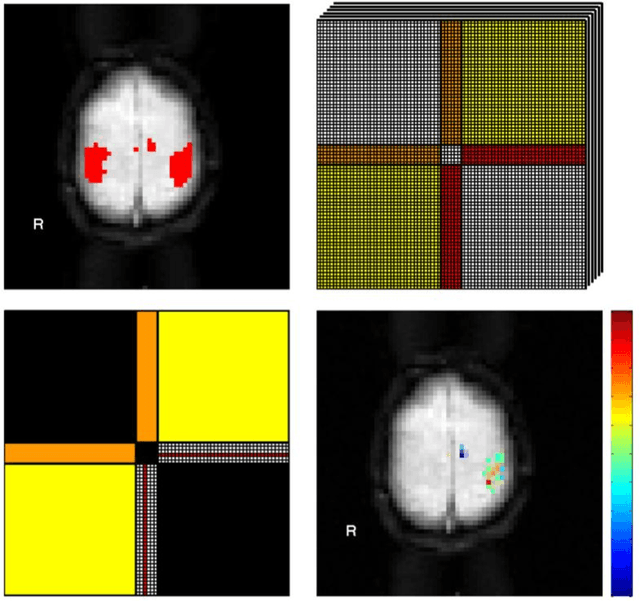

Abstract:We present a computational framework for analysis and visualization of non-linear functional connectivity in the human brain from resting state functional MRI (fMRI) data for purposes of recovering the underlying network community structure and exploring causality between network components. Our proposed methodology of non-linear mutual connectivity analysis (MCA) involves two computational steps. First, the pair-wise cross-prediction performance between resting state fMRI pixel time series within the brain is evaluated. The underlying network structure is subsequently recovered from the affinity matrix constructed through MCA using non-metric network partitioning/clustering with the so-called Louvain method. We demonstrate our methodology in the task of identifying regions of the motor cortex associated with hand movement on resting state fMRI data acquired from eight slice locations in four subjects. For comparison, we also localized regions of the motor cortex through a task-based fMRI sequence involving a finger-tapping stimulus paradigm. Finally, we integrate convergent cross mapping (CCM) into the first step of MCA for investigating causality between regions of the motor cortex. Results regarding causation between regions of the motor cortex revealed a significant directional variability and were not readily interpretable in a consistent manner across all subjects. However, our results on whole-slice fMRI analysis demonstrate that MCA-based model-free recovery of regions associated with the primary motor cortex and supplementary motor area are in close agreement with localization of similar regions achieved with a task-based fMRI acquisition. Thus, we conclude that our computational framework MCA can extract and visualize valuable information concerning the underlying network structure and causation between different regions of the brain in resting state fMRI.